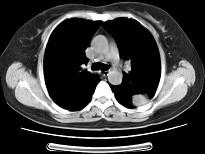

问题 女,52岁,左侧背痛1月,胸部CT如图,最可能的诊断为 ( )

选项 A.左肺中央型肺癌 B.左肺周围型肺癌 C.左肺感染 D.左肺炎性假瘤 E.肺隔离征

答案 D